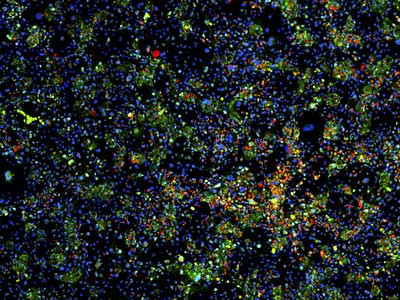

此前,這組研究人員曾開發(fā)了一種方法,將肝細(xì)胞與小鼠成纖維細(xì)胞精確混合,從而在體外維持肝細(xì)胞的正常功能。研究人員對(duì)此系統(tǒng)進(jìn)行了改進(jìn),并在其中對(duì)12,500種化合物進(jìn)行了大規(guī)模篩選,分析這些化合物對(duì)肝細(xì)胞生長和功能的影響。

肝臟是人體內(nèi)的重要器官,具有多種功能,包括藥物解毒作用、能量代謝、蛋白合成和膽汁生產(chǎn)等。研究人員對(duì)83種肝臟酶的表達(dá)水平進(jìn)行了檢測,以此評(píng)估肝細(xì)胞 的功能。他們篩選了八名組織捐獻(xiàn)者的數(shù)千個(gè)肝細(xì)胞,鑒定了能維持細(xì)胞功能或促進(jìn)細(xì)胞分裂的12種化合物。其中有兩種化合物,對(duì)年輕捐獻(xiàn)者的細(xì)胞效果特別 好。